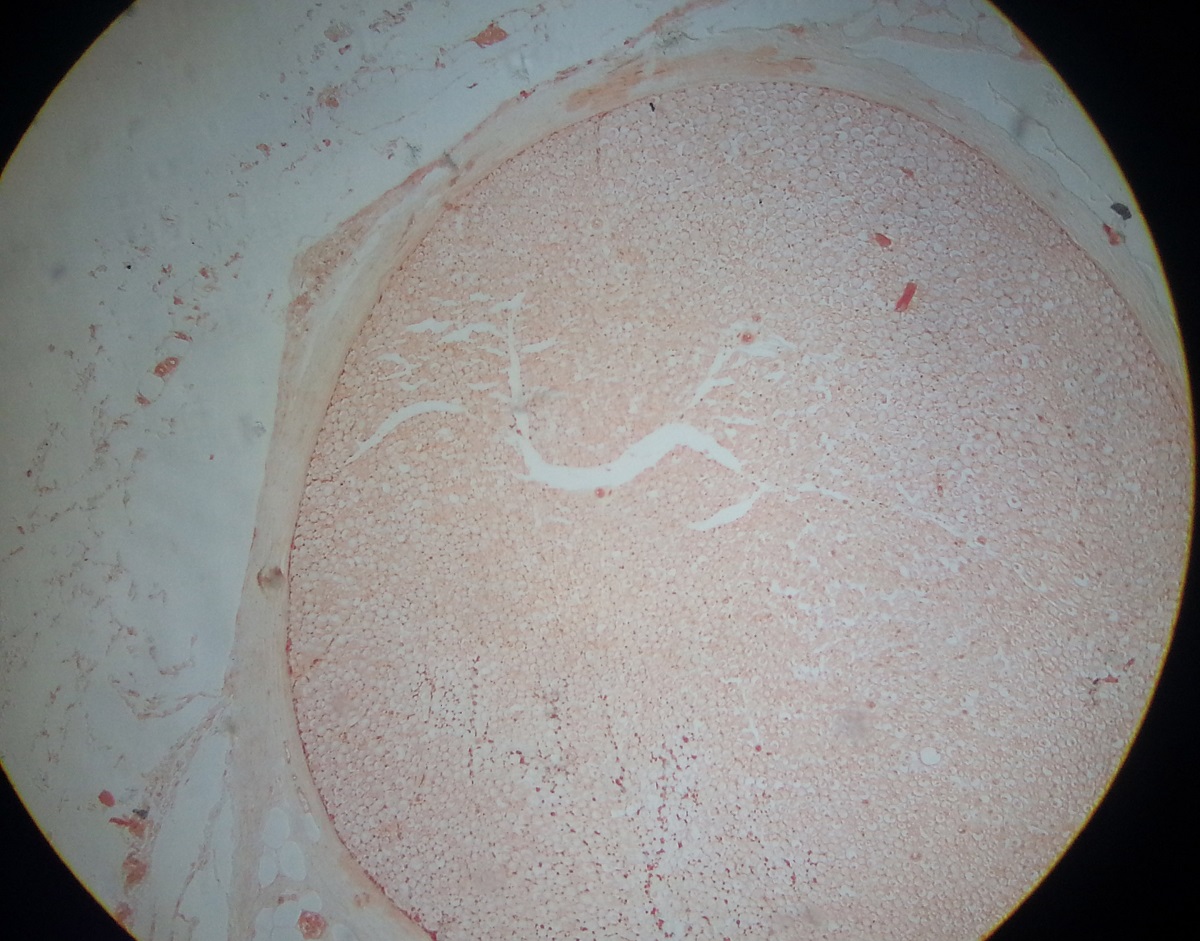

Thyroid

Consists of thyroid follicles and parafollicular cells(C cells)

Parafollicular cells are present in interstices between the follicles

Thyroid follicles has:

Cuboidal and flat lining epithelium (at inactive)

Columnar and tall lining epithelium( at active)

Homogenous colloid inside (stained pink)